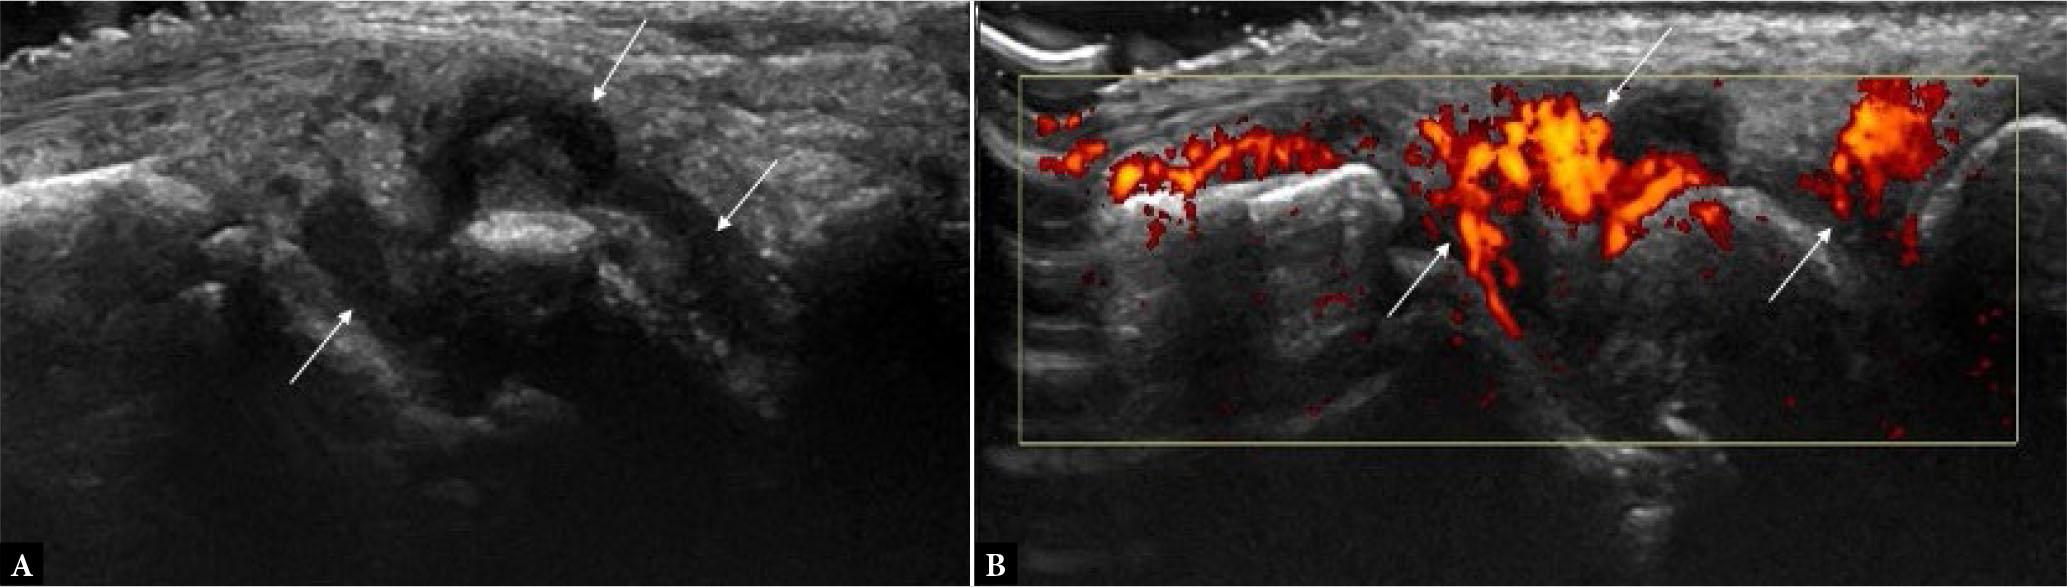

Fig. 4.

Greyscale (A) and power Doppler (B) long-axis US images of wrist joint depicting hypoechoic synovial proliferation (arrows in A) distending the joint capsule with diffuse vascularity (arrows in B)